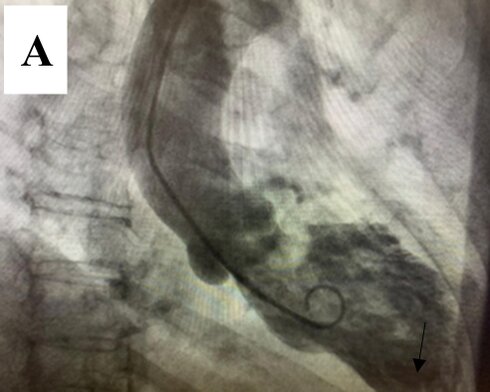

Left ventriculography demonstrated a normal-sized left ventricle with apical akinesis and basal hyperkinesis, resulting in the characteristic "apical ballooning" pattern seen in Takotsubo syndrome (TTS). An apical thrombus was also identified (Figure 4(a) and (b)).

Figure 4. Left ventriculography demonstrating apical akinesis and basal hyperkinesis, consistent with Takotsubo cardiomyopathy. An apical thrombus is clearly identified at the left ventricular apex (black arrow) in both diastole and systole views. (A) End-diastolic frame; (B) end-systolic frame.